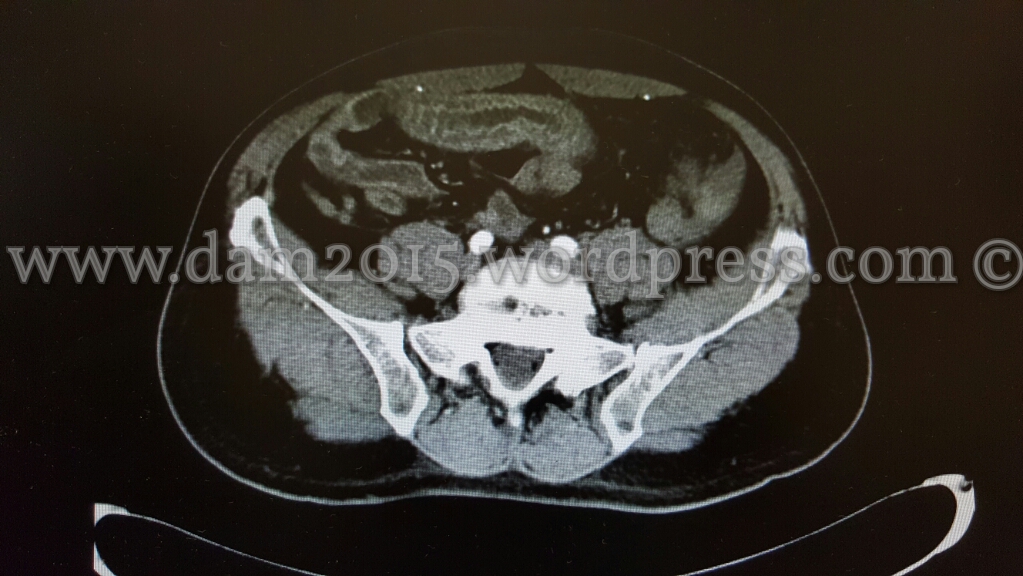

Eseguita TC addome che mostra ispessimento di alcune anse ideali in sede meso-ipogastrica ed in fossa iliaca destra come per infarcimento ematico.

Dopo MDC si osserva iperemia della mucosa a livello delle anse descritte e ridotta rappresentazione della vascolarizzazione del relativo mesentere, che presenta segni di imbibizione edemigena.

I reperti descritti sono suggestivi per quadro di infarto venoso intestinale.